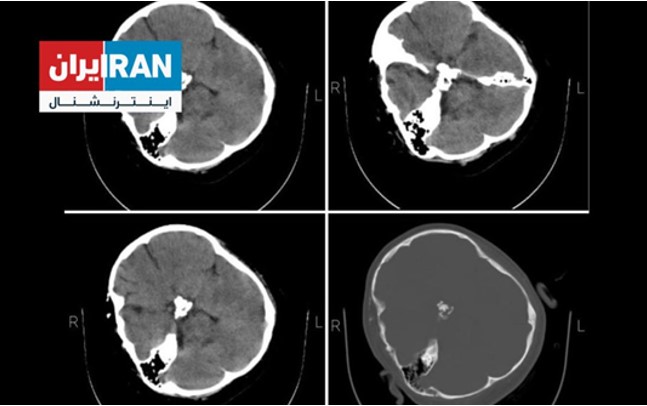

Die exklusiven Bilder von Mahsa Aminis CT-Scan, die von einer Hackergruppe veröffentlicht wurden, sollen einen Schädelbruch auf der rechten Seite ihres Kopfes aufgrund von Komplikationen zeigen, die durch einen direkten Schlag auf den Schädel verursacht wurden.

Tatsächlich ist Mahsa Amini bei der Verhaftung auf den Kopf geschlagen worden, was zu einer Hirnblutung, dem Koma und letztlich am selben Tag zu ihrem Hirntod führte.